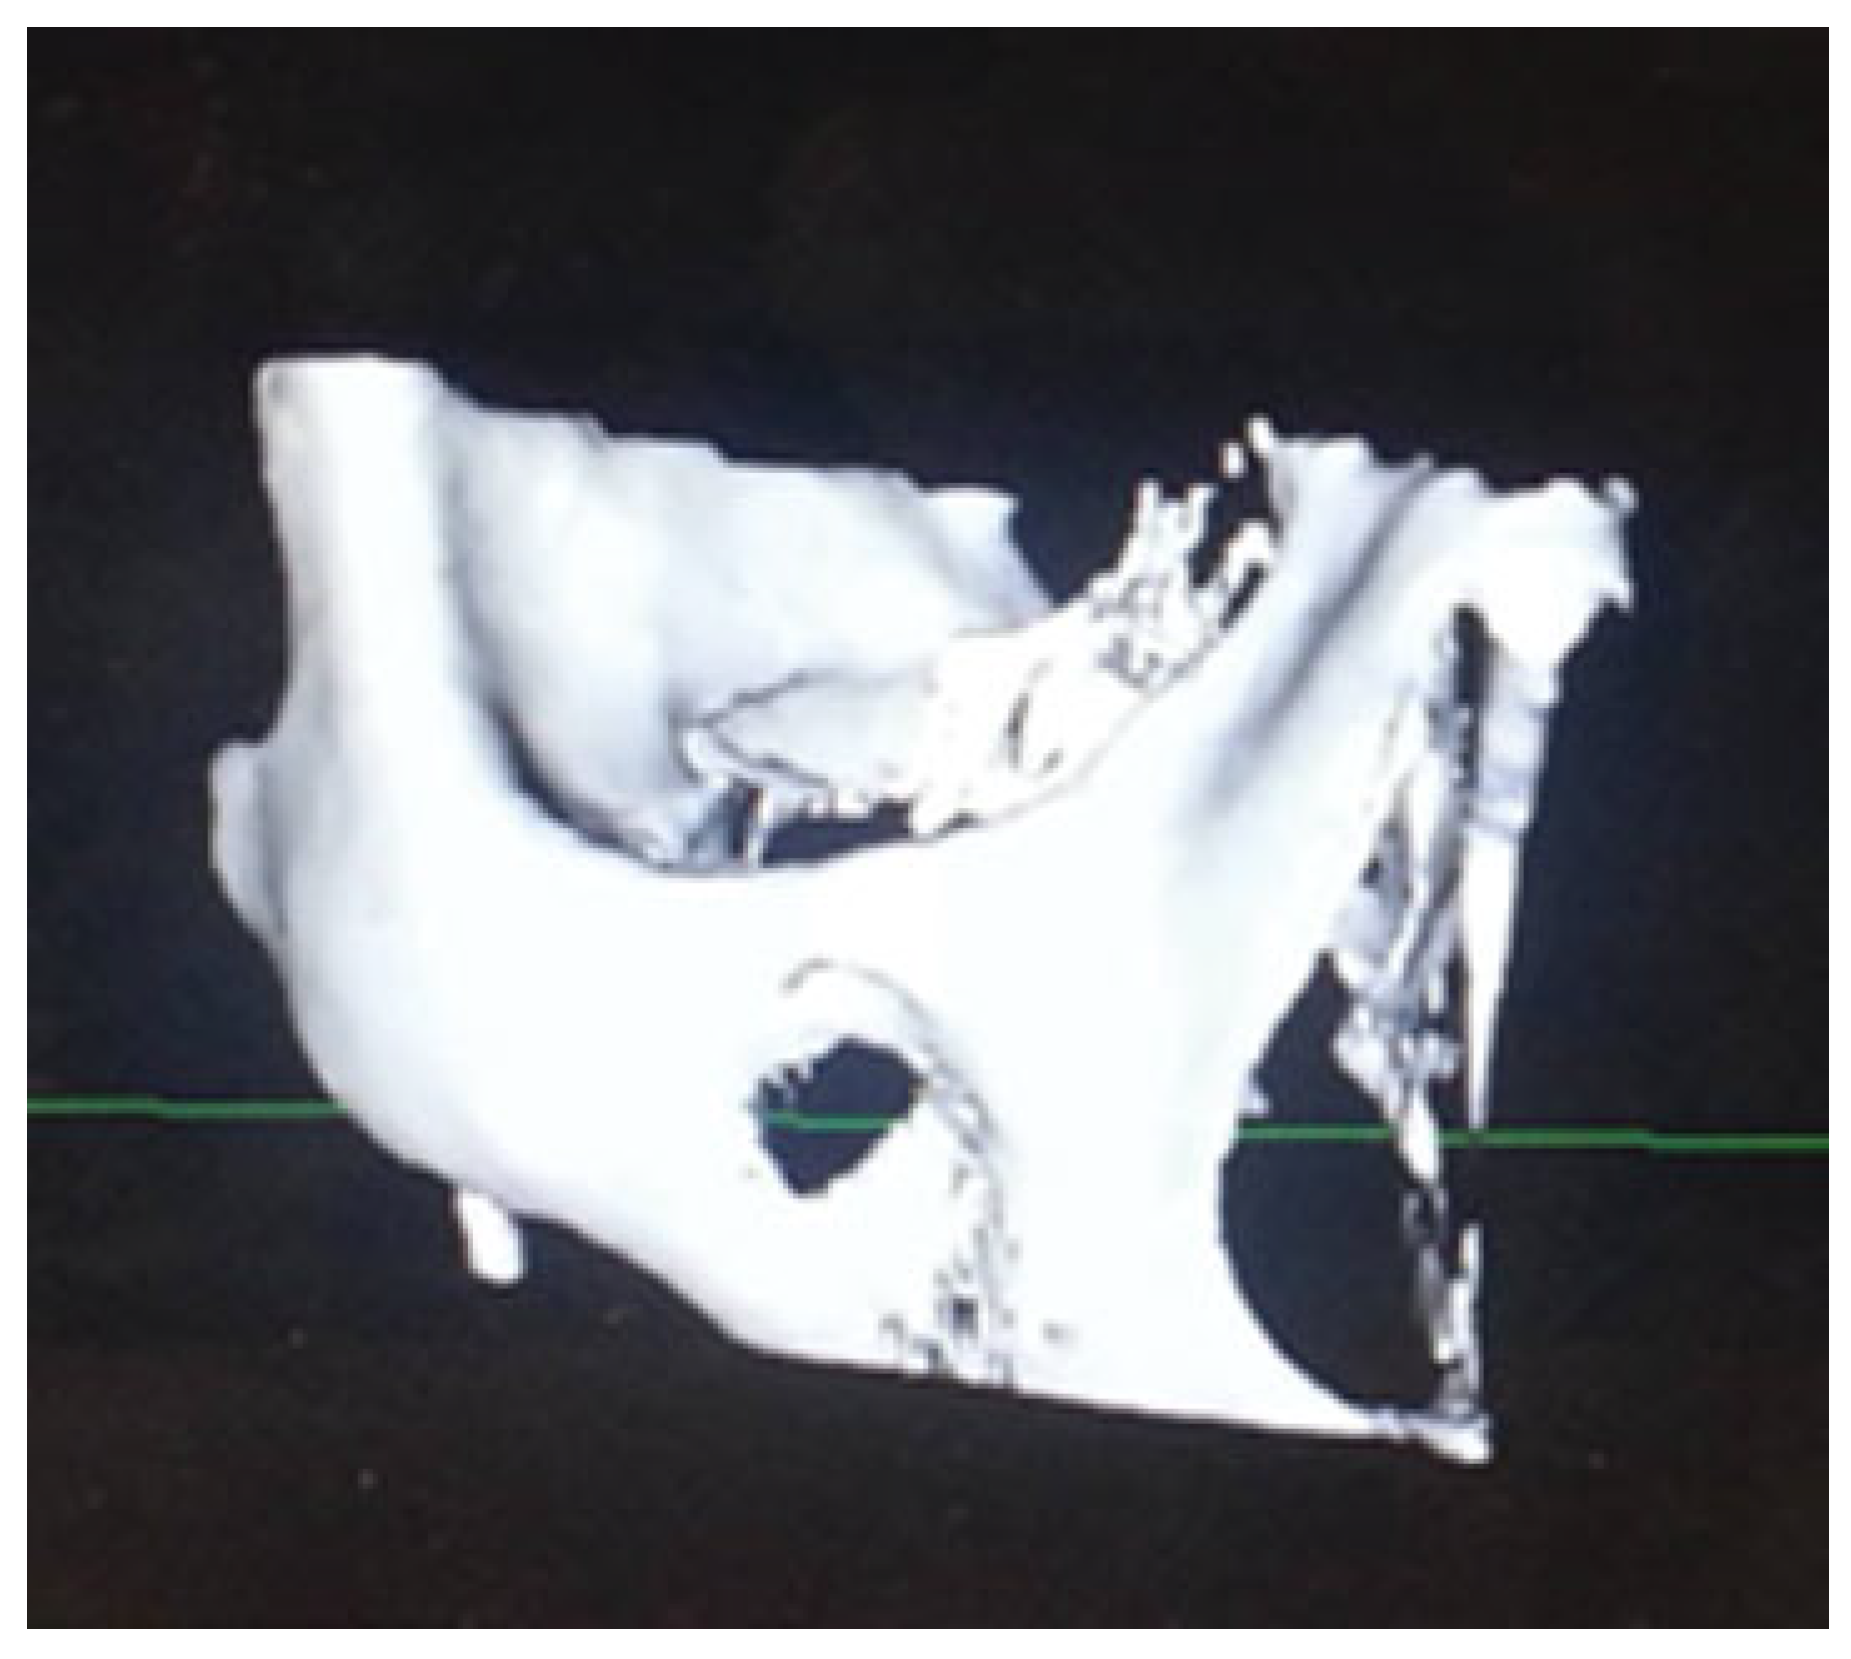

Computed tomography (CT) data were processed via an imaging software program (e.g., 3D slicer, Osirix [Osirix-Pixmeo, Bernex, Geneva, Switzerland]), cropped and then exported as a stereolithographic file (.stl) (Figure 1) which was then used for fabrication of a 3D model via 3D printing. CT orbital parameters used were 0.5 mm slice thickness, 0.4 mm increments, J70h kernel (Safire reconstruction), 120 kV, ref mAs 200, and Digital Imaging and Communication in Medicine (DICOM) data. A titanium orbital plate (Synthes [Synthes, Solothurn, Switzerland]) was subsequently adapted to the defect in each case before the procedure. The titanium orbital plate was sterilized before insertion and intraoperative CT imaging was used to assess final titanium plate position.

Figure 1.

“Cropped” computed tomographic data that is exported as an STL file to isolate the relevant anatomical site for reconstruction.